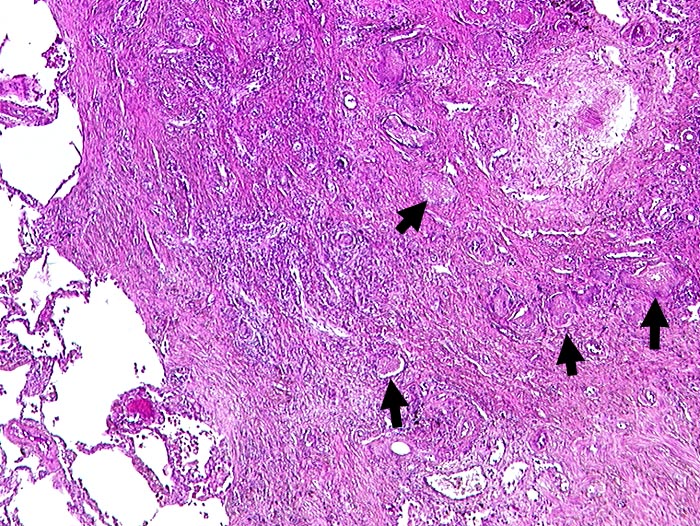

AP/ Pneumocystis carinii Pneumonie

Pneumocystis carinii Pneumonie

Entzündung infektiös

Lunge, Mediastinum mit Thymus

Lunge